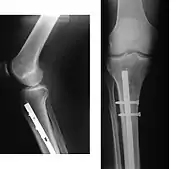

A cirurgia tem por objectivo restabelecer o alinhamento normal do osso, e manter esse alinhamento até a reparação da fratura. Permite também corrigir algumas lesões das partes moles, em especial vasos sanguíneos que possam ter rompido.

O restabelecimento da continuidade óssea por meio cirúrgico (osteossíntese) pode ser feito com recurso a várias técnicas, habitualmente com a utilização de placas e parafusos, varetas endomedulares ou Fios de Kirschner.